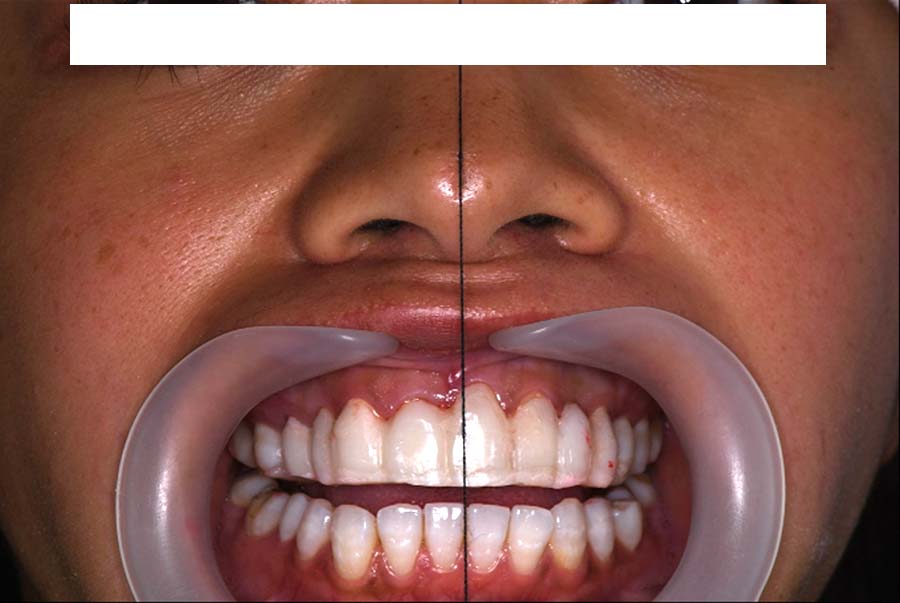

副子なし 副子あり

バイトアップ後

顔貌の変化

2024年 3月 初診時

2024年 10月10日

2025年 12月25日